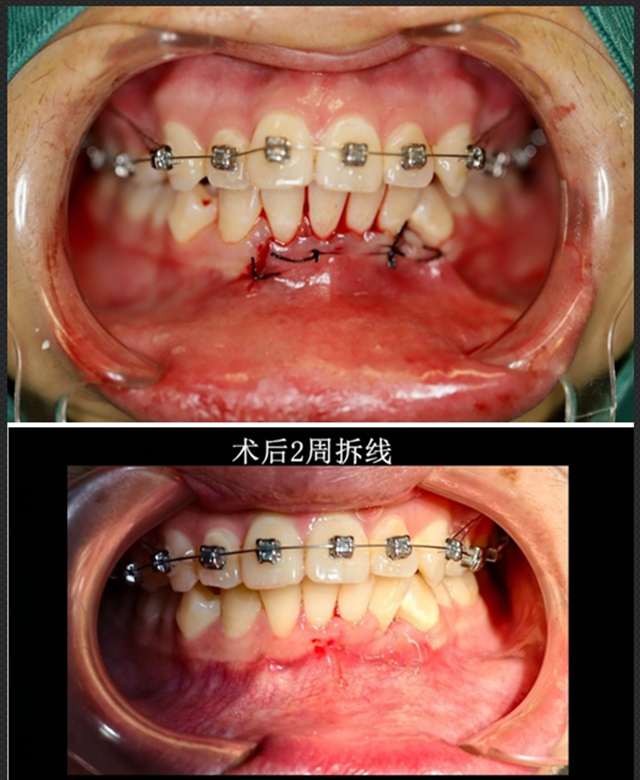

针对小陈情况,口腔诊疗中心立即开展了病例讨论,最终确定了“手术拔除+同期正畸规划”的个性化方案。

整个治疗过程就像一场精准的“排雷行动”,既要完成埋伏牙拔除,还要保证不损伤邻牙牙根及血管。

基于三维重建的结果,设计微创手术路径,避开重要解剖结构,拔除异位尖牙。

拔除埋伏牙后,立即衔接正畸方案,通过矫正关闭拔牙后留下的间隙,同时调整整体牙齿排列,帮助小陈恢复正常的咬合关系和面部协调度。

2周后拆线时,小陈伤口恢复非常理想,并未出现神经症状和其他不适。

目前小陈已进入正畸调整阶段,面部轮廓和咀嚼功能都有了显著改善。